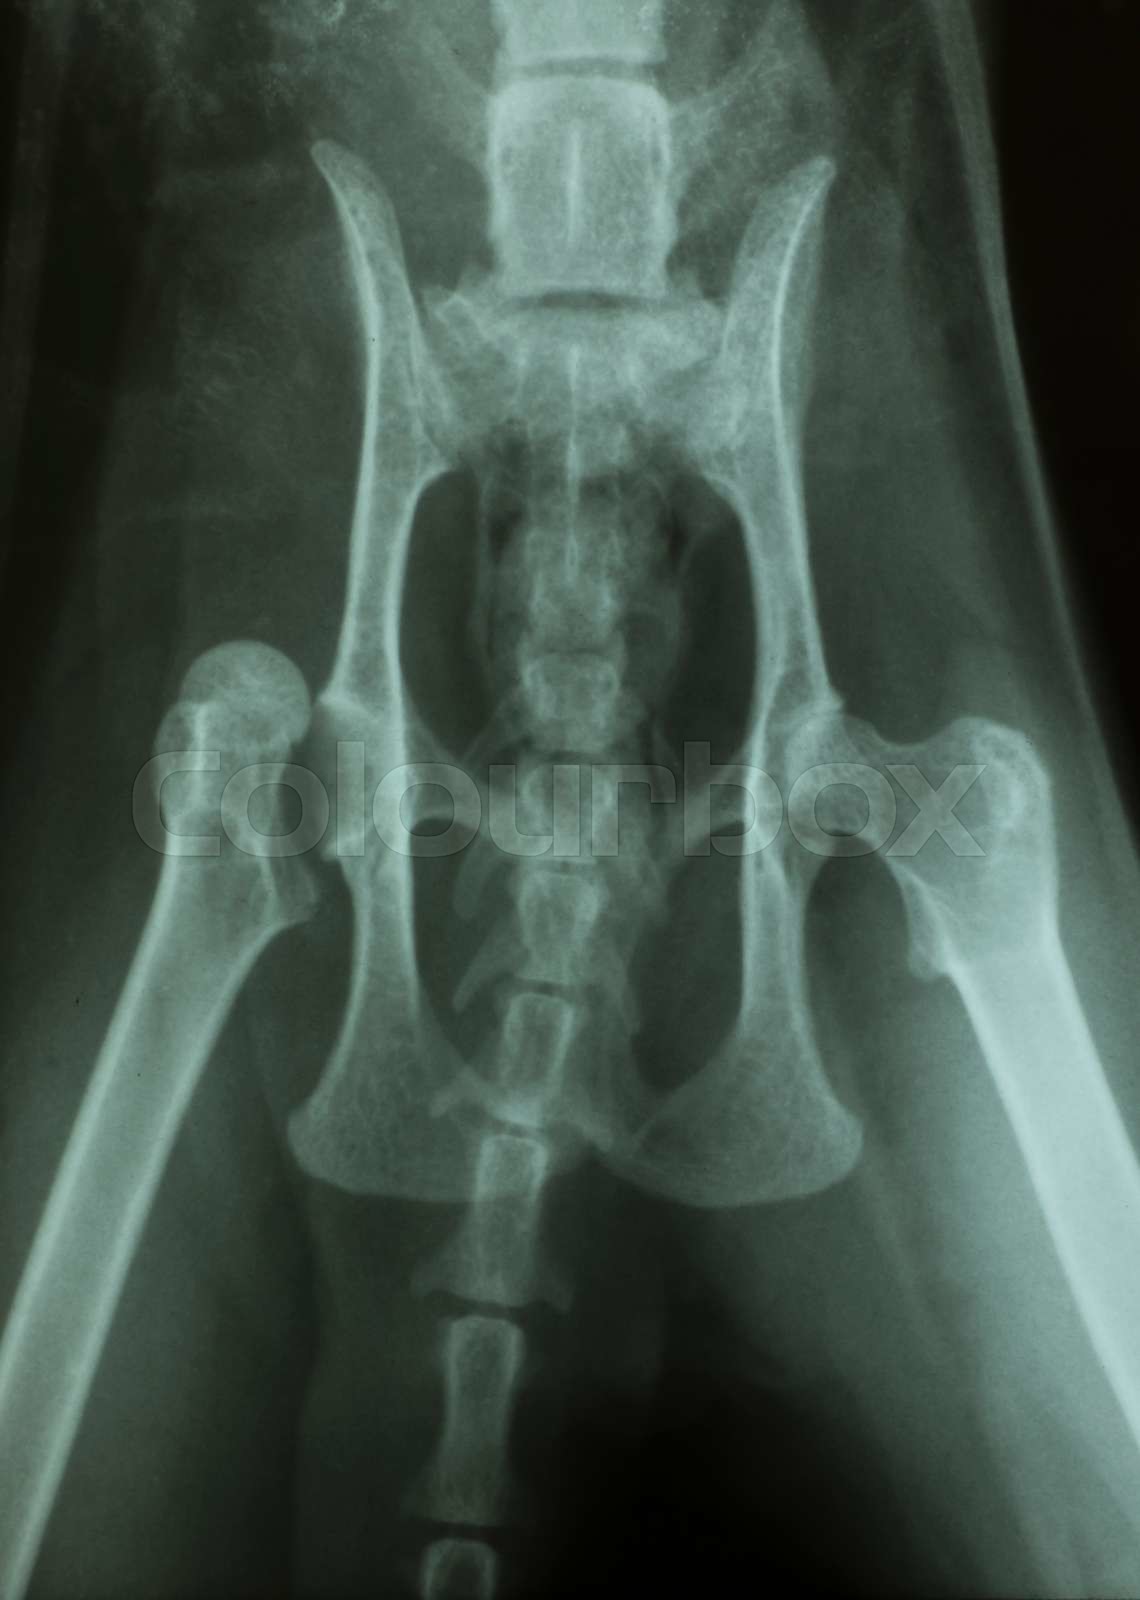

Luxation hip of a cat Xray Stock image Colourbox Normal Cat Hip Xray  It is designed as an aid.   it provides an overview of the imaging choices and techniques for different regions of the body, and gives examples of.  december 21st, 2020 | cats. It can be useful to obtain 2 orthogonal views of the contralateral limb for. You will be given examples of normal ones, and a given a chance. Normal Cat Hip Xray.